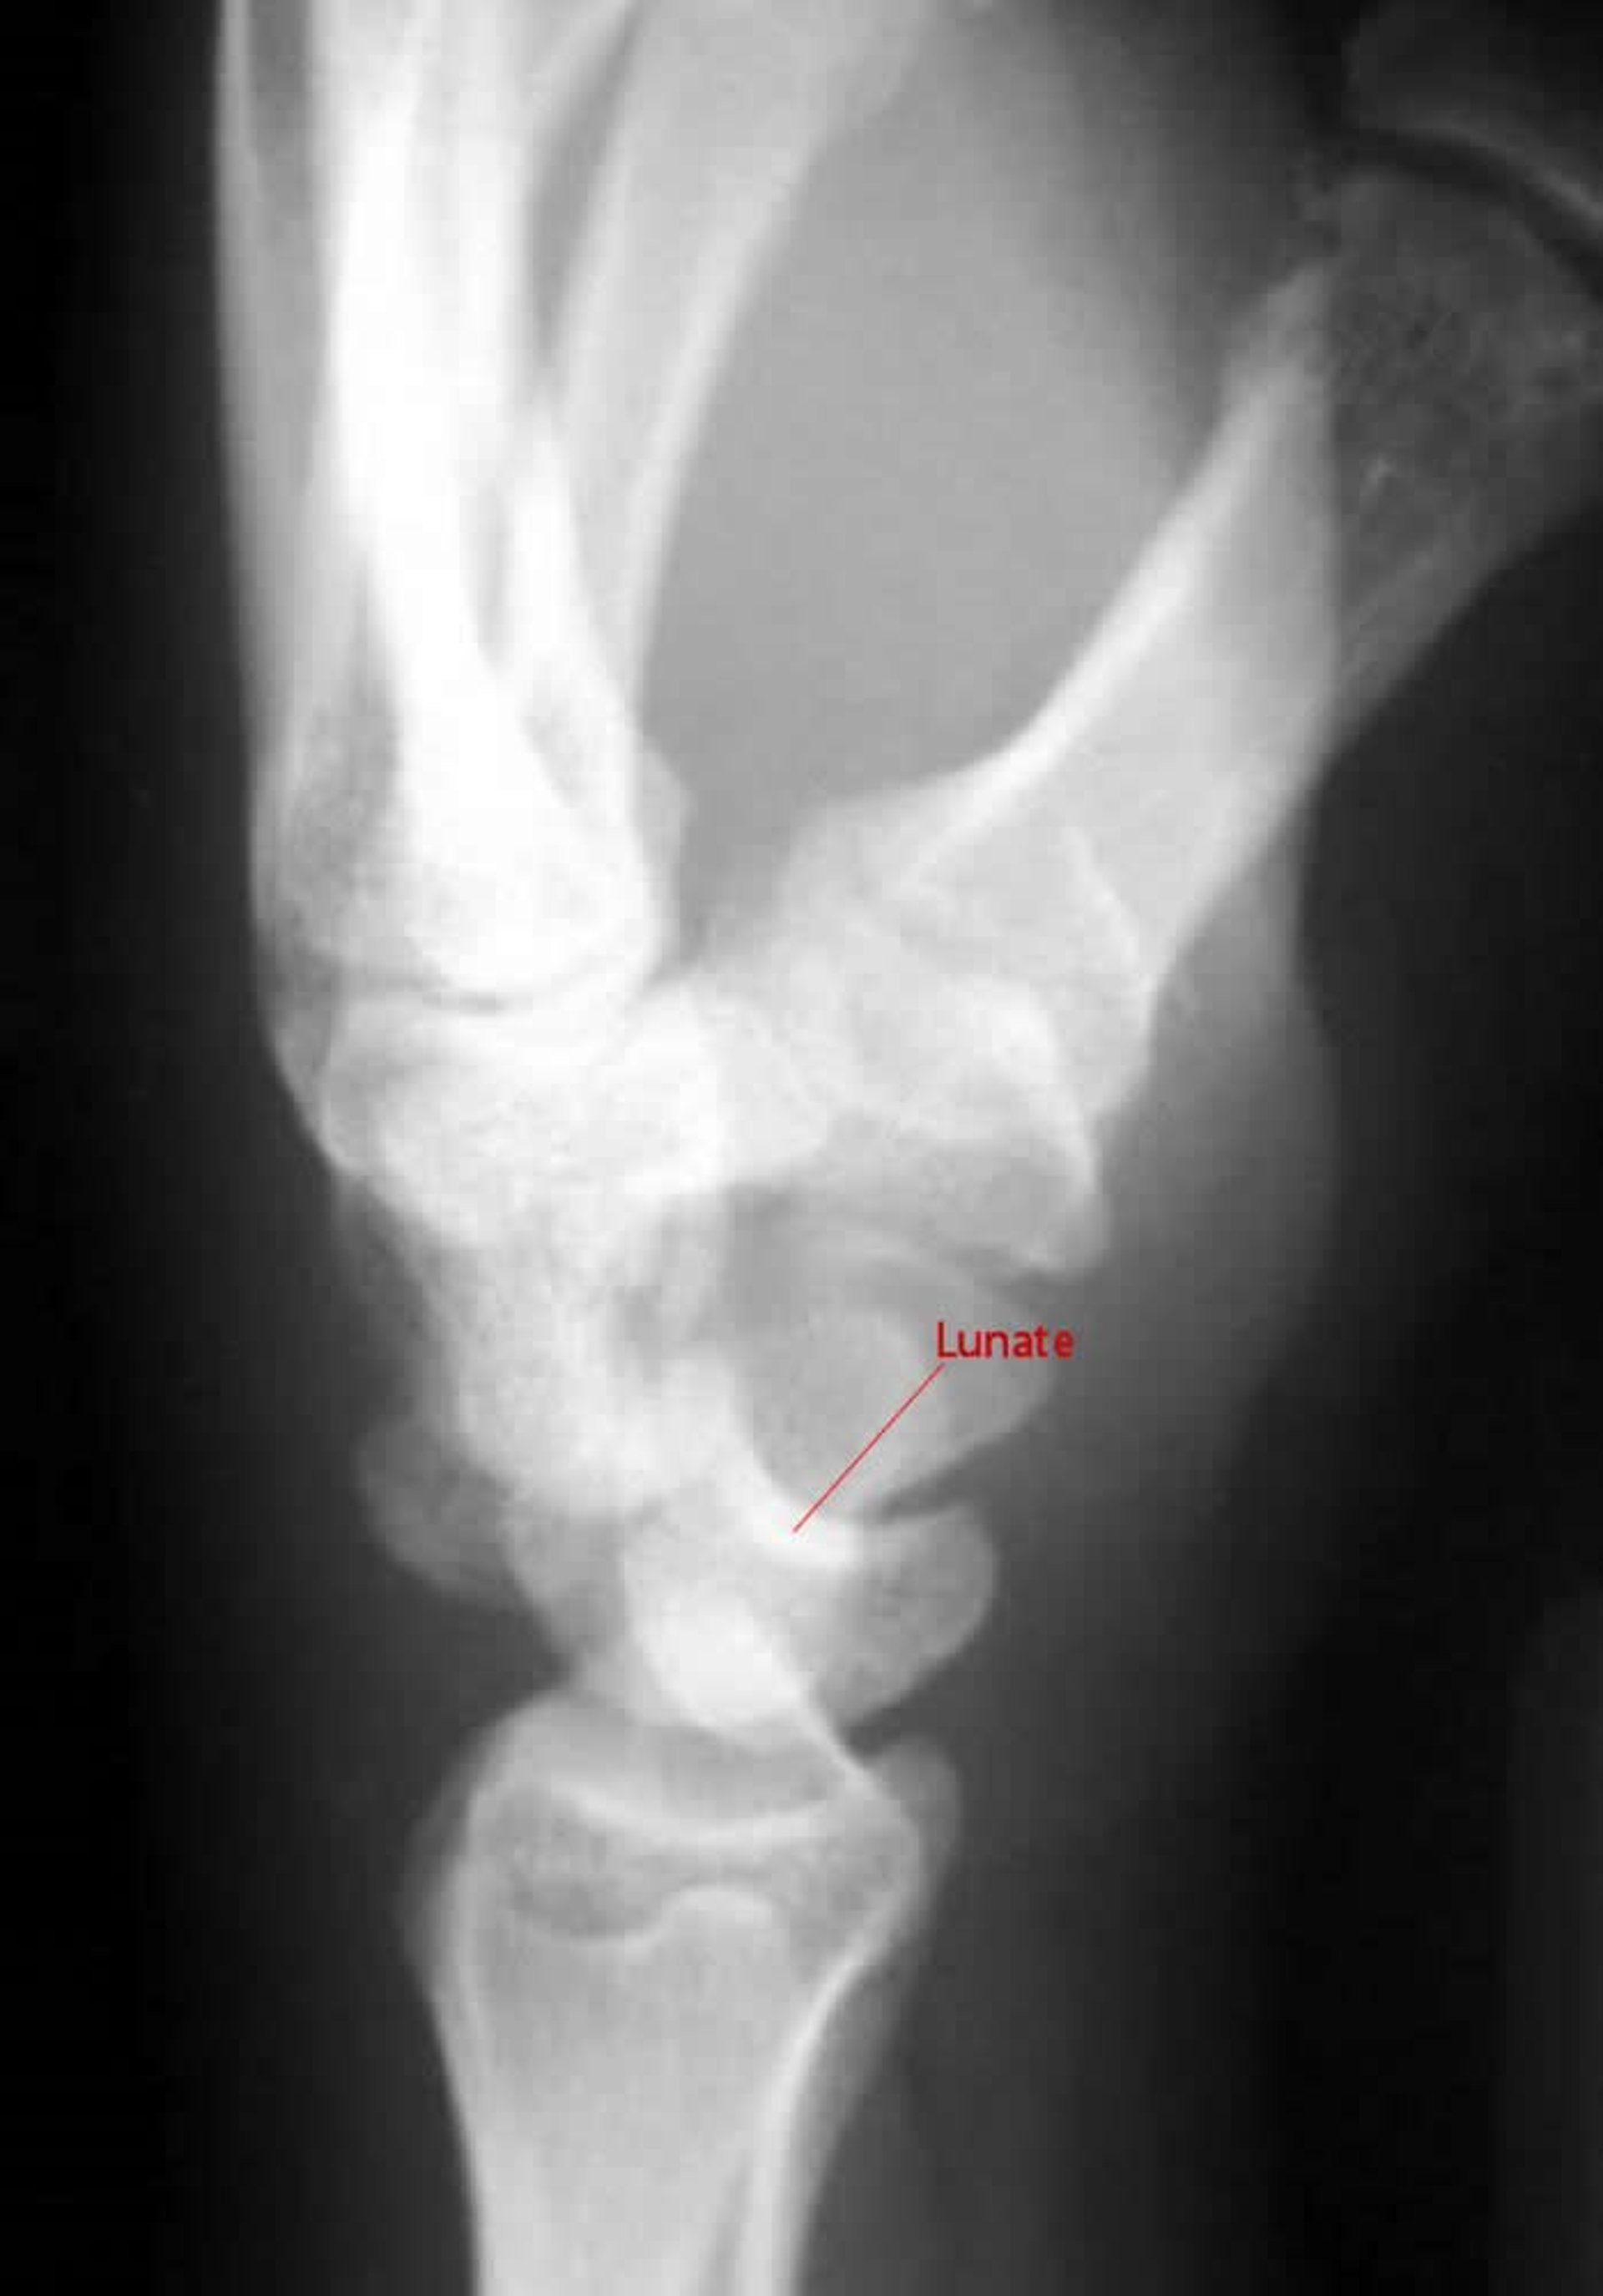

Lussazione perilunata

In una proiezione laterale di una lussazione perilunata, il capitato non si articola con il semilunare.